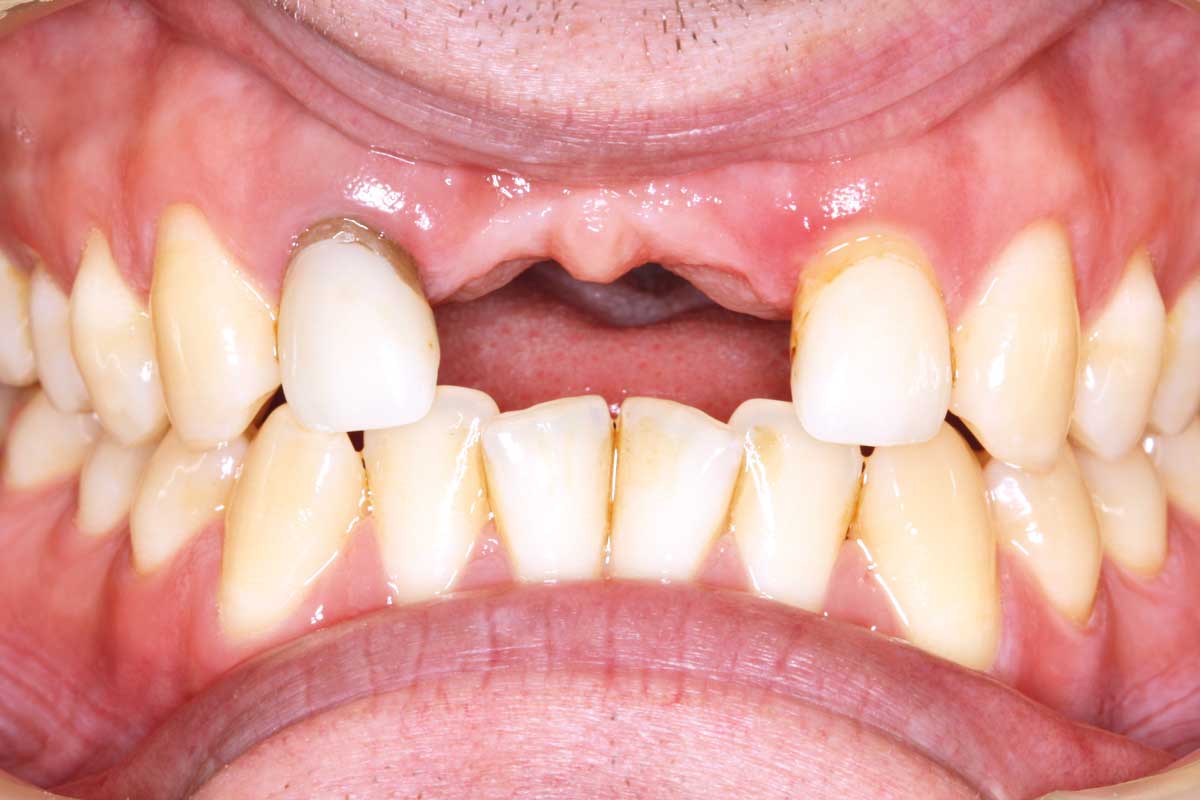

23/26 - Final clinical situation 12 months after augmentation

Ridge augmentation in the maxilla with maxgraft® bonebuilder in the aesthetic zone - Dr. M. Kristensen

24/26 - Final clinical situation 12 months after augmentation